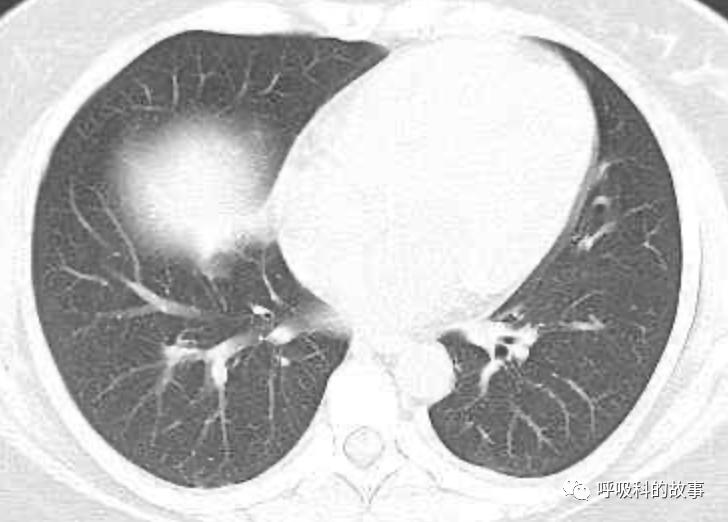

患者发热后行胸部CT检查(6月21日,住院第13天),可见两下肺有条片影,当时考虑是肺炎引起的发热。

可是在6月26日(往院第18天)仍持续发热的情况下复查肺部CT,肺部病灶已明显吸收了。那么患者发热的原因到底是什么呢?为什么患者高热的情况下血白细胞不升反降,C反应蛋白也没有明显增高?这个时候消化科医生也迷茫了,这可怎么办?于是请感染科和呼吸科医生一起会诊,共商计策。